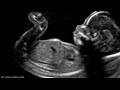

5 أشياء "غريبة" يقوم بها كل جنين في رحم أمه

الجنين يقوم بأمور غريبة في بطن أمه

لا يتذكر الناس شيئا عما فعلوه حين كانوا في أرحام أمهاتهم، لكن باحثين في الطب كشفوا عدة أمور يقوم بها أي جنين قبل قدومه إلى الحياة، حسب موقع "سكاي نيوز".